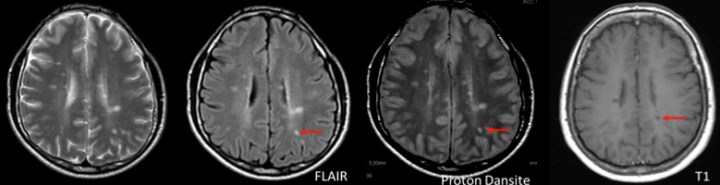

T2 lezyonları ve “kirli ak madde”

MS’te tipik lezyonlar geleneksel olarak T2 ağırlıklı sekansta saptanır. Ancak T2 lezyonları özgül değildir. MS için tipik T2 lezyonları 2 mm’den büyük, ovoid veya yuvarlak odaklardır. T2 hiperintens görüntü şu durumlarda ortaya çıkabilir:

Konvansiyonel T2 lezyonları, aynı zamanda diffüz, büyük ve düzensiz hiperintens alanları da kapsar; bu görünüme “kirli ak madde” adı verilir. Bunlar sınırları belirsiz, özellikle oksipital horn çevresine yerleşen geniş lezyonlardır ve RRMS hastalarının yaklaşık %17’sinde tanımlanır.

İMG – MRG-5: “Kirli ak madde” görünümü.

İMG – MRG-6: Jukstakortikal lezyonlar.